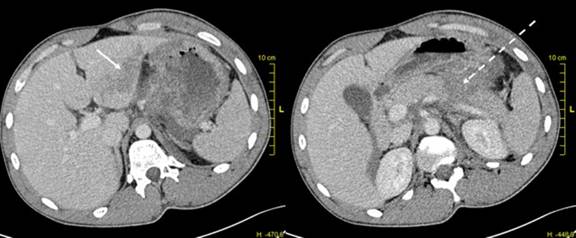

In the resuscitation room of our centre we received a 24-year-old man without any previous medical history, after a road traffic accident. He fell of his motorcycle with unclear circumstances; he did not remember the event because of an alcohol abuse. Assessment in emergency room revealed stable hemodynamic signs but a marked tenderness with focalized guarding in the epigastric region. There were diffuse contusions of the thoracic and abdominal wall. The rest of the clinical examination was normal. Laboratory analysis indicated a ten-fold increase of liver enzymes and elevated lipases at 337 U/L (reference range:10-150 U/L). Thoracoabdominal computed tomography (CT) showed a hemoperitoneum, a moderate contusion of the left liver, and a complete fracture between the body and the tail of the pancreas (Grade III) [10] (Figure 1).

Figure 1. CT scan showing a moderate contusion of the left liver (arrow), and a complete fracture between the body and the tail of the pancreas with an hematoma in front of the splenic vein (dotted arrow). |